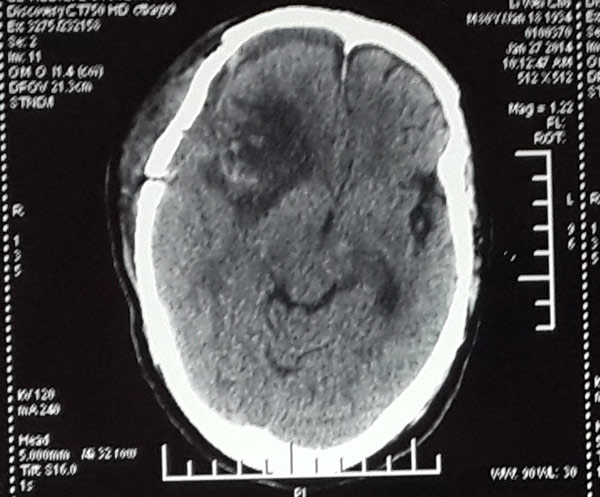

通过手术探查,医生发现肿瘤侵占了整个脑颅近一半的空间,“李大爷的右边大脑组织已经受到肿瘤的挤压变形,再不手术李大爷很有可能出现出现生命危险。”神经外科张雅轩医生介绍。

在范学政主任以及张雅轩医生等神经外科医护团队三个多小时的合力奋战,手术顺利完成,脑瘤组织被完全切除,挽救了李大爷的生命。

术后脑膜瘤被完整移除